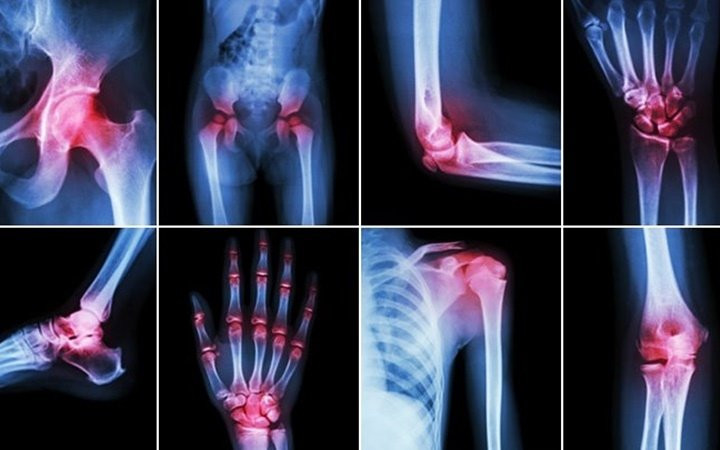

Viêm khớp: Mùa đông cũng là khắc tinh của những người bị đau khớp. Những người bị viêm khớp cho biết, các khớp xương của họ cứng hơn và bị đau hơn vào mùa đông. Tuy nhiên, không có cơ sở nào chứng minh rằng thời tiết lạnh hơn sẽ gây ra bệnh đau khớp. Một số chuyên gia cho rằng, con người bị trầm cảm hơn trong thời tiết mùa đông, khiến họ cảm nhận nỗi đau sâu sắc hơn. Các chuyên gia đưa ra lời khuyên rằng, việc tập thể dục hàng ngày có thể giúp cải thiện thể chất và cả tinh thần của người bệnh. Bơi lội là môn thể thao lý tưởng cho những người có vấn đề về khớp. (Ảnh: KT)